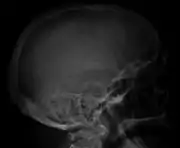

The diagnostic examination of a person with suspected multiple myeloma typically includes a skeletal survey. This is a series of X-rays of the skull, axial skeleton, and proximal long bones. Myeloma activity sometimes appears as "lytic lesions" (with local disappearance of normal bone due to resorption) or as "punched-out lesions" on the skull X-ray ("raindrop skull"). Lesions may also be sclerotic, which is seen as radiodense.[70] Overall, the radiodensity of myeloma is between −30 and 120 Hounsfield units (HU).[71] Magnetic resonance imaging is more sensitive than simple X-rays in the detection of lytic lesions, and may supersede a skeletal survey, especially when vertebral disease is suspected. Occasionally, a CT scan is performed to measure the size of soft-tissue plasmacytomas. Bone scans are typically not of any additional value in the workup of people with myeloma (no new bone formation; lytic lesions not well visualized on bone scan).

Skull X-ray showing multiple lucencies due to multiple myeloma